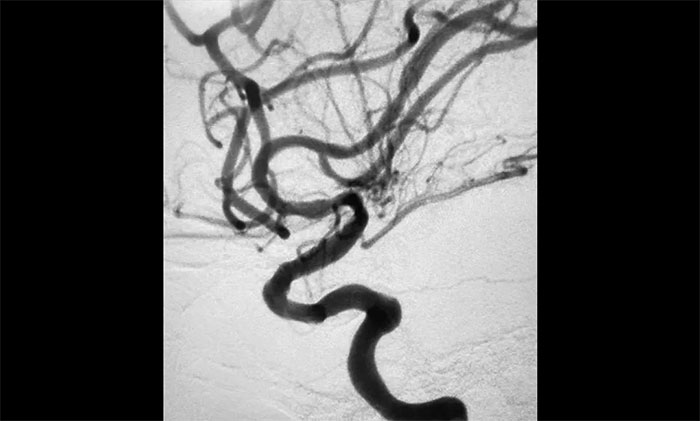

▲術(shù)后DSA影像:左側(cè)頸內(nèi)動(dòng)脈血流恢復(fù)

術(shù)中腦血管造影可見:左側(cè)頸內(nèi)動(dòng)脈眼動(dòng)脈段以遠(yuǎn)閉塞……余血管未見明顯異常。張琪博士在劉春、周林華、李喆醫(yī)生協(xié)助下,通過右側(cè)股動(dòng)脈穿刺,將微導(dǎo)管、微導(dǎo)絲送達(dá)左側(cè)大腦中動(dòng)脈M1段,經(jīng)多次抽吸+支架拉栓,順利取出血栓。造影顯示,頸內(nèi)動(dòng)脈眼動(dòng)脈段血流恢復(fù)。

隨后,微導(dǎo)絲超選至左側(cè)大腦中動(dòng)脈M1段遠(yuǎn)端,并以多枚球囊擴(kuò)張殘余重度狹窄處,造影提示狹窄較前明顯改善,遠(yuǎn)端血流改善明顯。最后順利放入支架,造影提示支架貼壁良好,支架內(nèi)血流通暢,遠(yuǎn)端血流良好,手術(shù)順利完成。